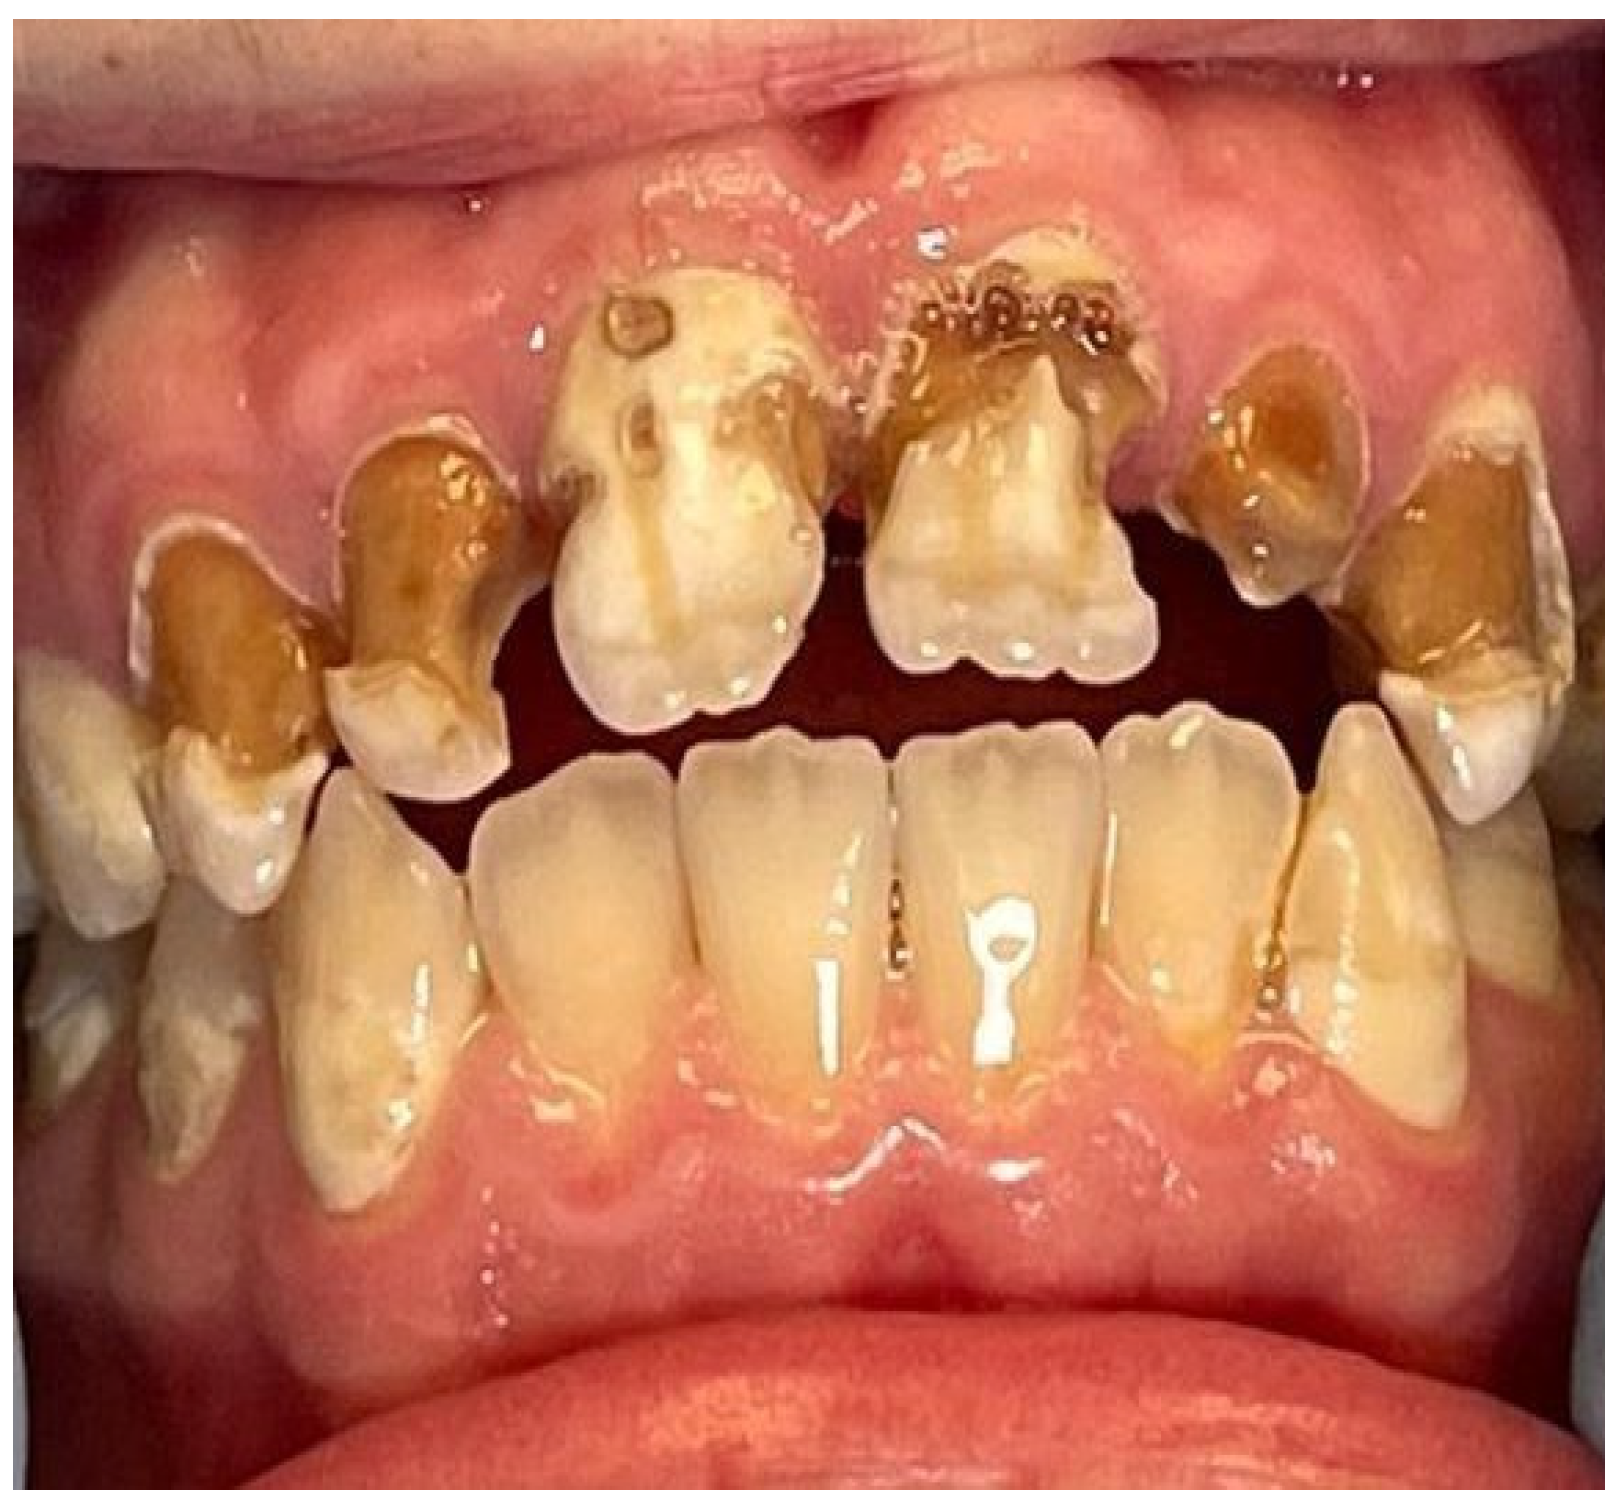

2. Case Report